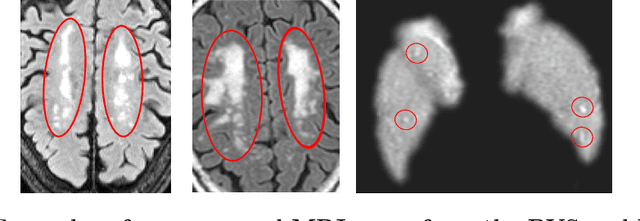

Abstract:Registration is a core component of many imaging pipelines. In case of clinical scans, with lower resolution and sometimes substantial motion artifacts, registration can produce poor results. Visual assessment of registration quality in large clinical datasets is inefficient. In this work, we propose to automatically assess the quality of registration to an atlas in clinical FLAIR MRI scans of the brain. The method consists of automatically segmenting the ventricles of a given scan using a neural network, and comparing the segmentation to the atlas' ventricles propagated to image space. We used the proposed method to improve clinical image registration to a general atlas by computing multiple registrations and then selecting the registration that yielded the highest ventricle overlap. Methods were evaluated in a single-site dataset of more than 1000 scans, as well as a multi-center dataset comprising 142 clinical scans from 12 sites. The automated ventricle segmentation reached a Dice coefficient with manual annotations of 0.89 in the single-site dataset, and 0.83 in the multi-center dataset. Registration via age-specific atlases could improve ventricle overlap compared to a direct registration to the general atlas (Dice similarity coefficient increase up to 0.15). Experiments also showed that selecting scans with the registration quality assessment method could improve the quality of average maps of white matter hyperintensity burden, instead of using all scans for the computation of the white matter hyperintensity map. In this work, we demonstrated the utility of an automated tool for assessing image registration quality in clinical scans. This image quality assessment step could ultimately assist in the translation of automated neuroimaging pipelines to the clinic.

Abstract:Weakly supervised detection methods can infer the location of target objects in an image without requiring location or appearance information during training. We propose a weakly supervised deep learning method for the detection of objects that appear at multiple locations in an image. The method computes attention maps using the last feature maps of an encoder-decoder network optimized only with global labels: the number of occurrences of the target object in an image. In contrast with previous approaches, attention maps are generated at full input resolution thanks to the decoder part. The proposed approach is compared to multiple state-of-the-art methods in two tasks: the detection of digits in MNIST-based datasets, and the real life application of detection of enlarged perivascular spaces -- a type of brain lesion -- in four brain regions in a dataset of 2202 3D brain MRI scans. In MNIST-based datasets, the proposed method outperforms the other methods. In the brain dataset, several weakly supervised detection methods come close to the human intrarater agreement in each region. The proposed method reaches the lowest number of false positive detections in all brain regions at the operating point, while its average sensitivity is similar to that of the other best methods.

Abstract:Enlarged perivascular spaces (EPVS) in the brain are an emerging imaging marker for cerebral small vessel disease, and have been shown to be related to increased risk of various neurological diseases, including stroke and dementia. Automatic quantification of EPVS would greatly help to advance research into its etiology and its potential as a risk indicator of disease. We propose a convolutional network regression method to quantify the extent of EPVS in the basal ganglia from 3D brain MRI. We first segment the basal ganglia and subsequently apply a 3D convolutional regression network designed for small object detection within this region of interest. The network takes an image as input, and outputs a quantification score of EPVS. The network has significantly more convolution operations than pooling ones and no final activation, allowing it to span the space of real numbers. We validated our approach using a dataset of 2000 brain MRI scans scored visually. Experiments with varying sizes of training and test sets showed that a good performance can be achieved with a training set of only 200 scans. With a training set of 1000 scans, the intraclass correlation coefficient (ICC) between our scoring method and the expert's visual score was 0.74. Our method outperforms by a large margin - more than 0.10 - four more conventional automated approaches based on intensities, scale-invariant feature transform, and random forest. We show that the network learns the structures of interest and investigate the influence of hyper-parameters on the performance. We also evaluate the reproducibility of our network using a set of 60 subjects scanned twice (scan-rescan reproducibility). On this set our network achieves an ICC of 0.93, while the intrarater agreement reaches 0.80. Furthermore, the automatic EPVS scoring correlates similarly to age as visual scoring.